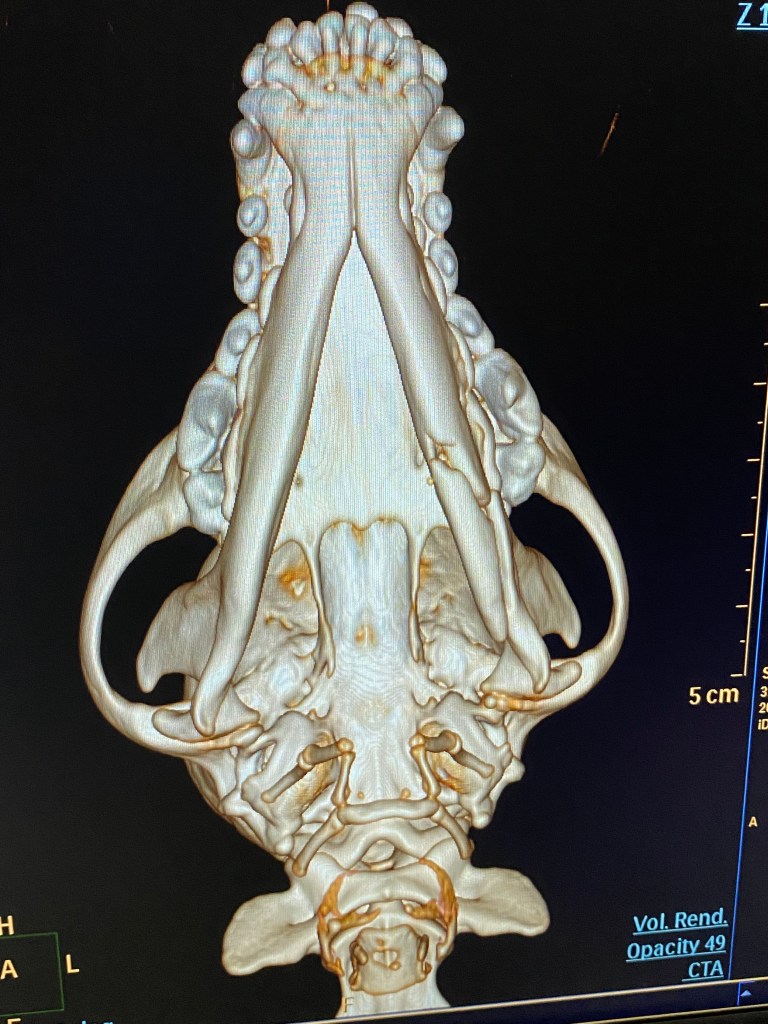

Another patient arrives – a dog that sustained a jaw fracture after chasing a moose (not a mouse….). Here another anaesthesia and thick cerclage wire is needed to both stabilise the fracture and hopefully safe the canine tooth. Luckily the root was undamaged.